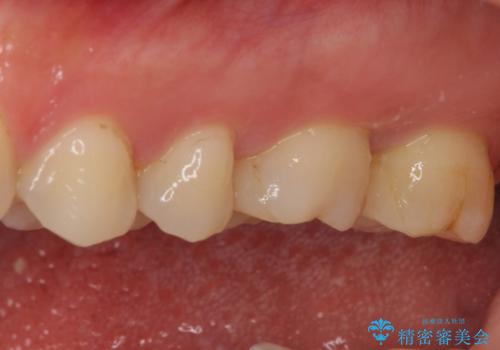

強い咬合力を負担する第一大臼歯であるため、根管治療後は速やかにオールセラミッククラウンにて補綴治療を行うこととしました。